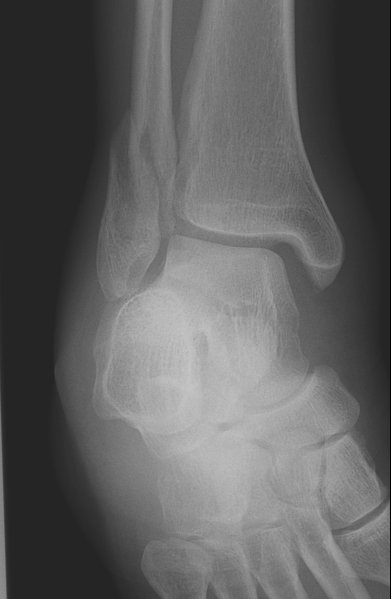

Return to Weber B Fracture